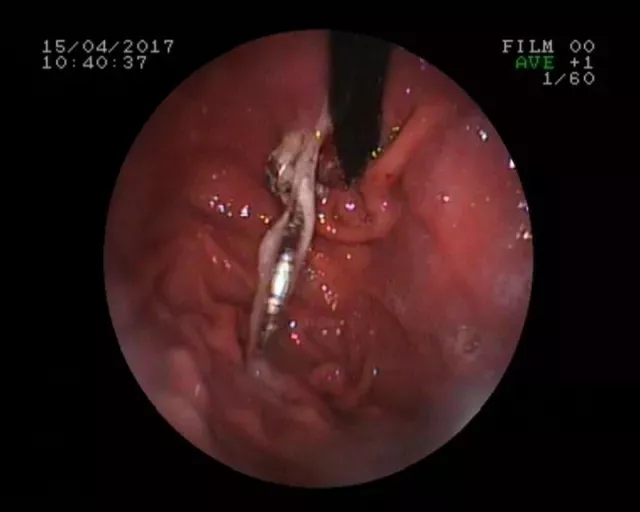

11月21号下午,一名5岁的小朋友在玩耍时误服一颗泡大珠,患儿家长得知后迅速来我院儿外科急诊就诊,考虑泡大珠遇水可膨胀至4-6cm大小,若不慎排入肠道可能引发肠梗阻,需面临开腹手术的风险。儿外科急诊医生立即开通绿色通道,电话通知胃肠镜室医生,胃肠镜室医生在向患儿家属交代病情及相关风险后立即联系麻醉科,待一切准备就绪后在全身麻醉下对患儿行急诊内镜下异物取出术。

进镜后于胃底体交界处可见一蓝色圆形异物(泡大珠),此时泡大珠已膨胀至1.5cm×1.5cm,脆性增加,为防止在取出过程中泡大珠碎裂,不能完整取出可能会对患儿身体造成二次伤害,术中使用了一次性网兜套圈,完整将异物套住,顺利取出。术后,再次观察泡大珠完整,患儿无不适。